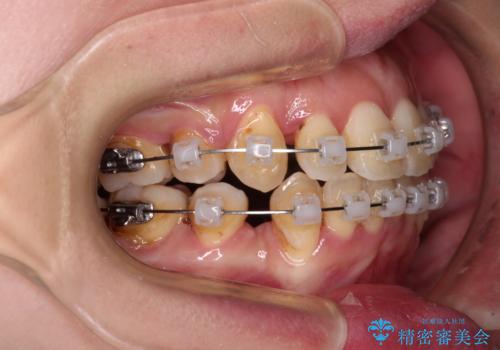

- クリアブラケット

- 2年9ヶ月

治療期間全体を通して歯の移動スピードがゆっくりであったので、当初予定よりも1年ほど長い、3年間を要することとなりました。